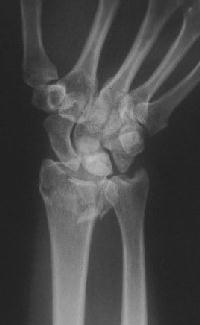

Clinical Example: Distraction plate fixation of distal radius fracture

distal radius fracture

distraction plate